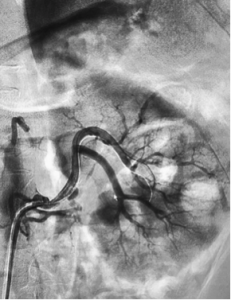

Bệnh nhân (BN) nam 53 tuổi, vào viện vì đau hông lưng trái đột ngột. Tiền sử: THA – rối loạn lipid máu điều trị không đều. Bệnh nhân đau hông lưng trái lan ra trước từng cơn 4 ngày, kèm tiểu buốt, tiểu máu, không sốt. Bệnh nhân nhập viện trong tình trạng da, niêm mạc bình thường, HA: 120/70mmHg, nhiệt độ 36,5 độ C, vỗ hông lưng (-), bụng mềm, các bộ phận khác không có gì đặc biệt. Xét nghiệm máu Ure 6,2 mmol/l, creatinin 155 µmol/l, AST/ALT 70/96 U/l, máu lắng tăng (giờ 1: 75mm, giờ 2: 87mm); nước tiểu có protein niệu, không có hồng cầu, bạch cầu; các xét nghiệm khác, siêu âm bụng, X quang phổi bình thường. BN được chỉ định chụp CT ổ bụng có tiêm cản quang, trên phim chụp CT bụng thấy hình ảnh hai động mạch thận trái, động mạch trước bể tách cao hơn và có hình ảnh bóc tách ở vị trí 1/3 giữa, có lòng giả, thành động mạch sau vị trí bóc tách dày do huyết khối trong thành, nhu mô 1/3 trên kém ngấm thuốc do thiếu máu, có vài ổ hoại tử không ngấm thuốc cản quang kích thước dưới 10mm (hình 1). Động mạch sau bể tách thấp hơn, thành mạch và lòng mạch bình thường, không có hình ảnh thiếu máu cực dưới thận. BN được điều trị nội khoa 3 ngày với Aspirin 81mg/ngày, clopidogrel (Plavix) 75mg/ngày, rosuvastatin (Crestor) 10mg/ngày, paracetamol 1g/ngày. Chụp mạch số hoá xoá nền động mạch thận cho thấy thấy hình ảnh tương tự với cắt lớp vi tính, điểm bóc tách của động mạch trước bể bắt đầu từ cách gốc 10mm, kéo dài khoảng 15 mm gây hẹp lòng thật, lòng giả còn lưu thông thuốc cản quang kích thước khoảng 3x2mm. Tiến hành can thiệp đặt một stent Biomine 4 x 19mm qua đoạn mạch thận tổn thương (hình 2). Sau đặt stent 1 ngày, BN không đau thắt lưng, không rối loạn tiểu tiện, thăm khám các bộ phận không thấy bất thường; xét nghiệm ure: 6,4 mmol/l, creatinin 115 µmol/l, AST/ALT 81/136 U/l, tổng phân tích nước tiểu bình thường. BN ra viện tiếp tục dùng clopidogrel/ aspirin (Duoplavin) 75/100mg/ngày, Crestor 10mg/ngày. Sau 1 tháng, BN tái khám, xét nghiệm ure 5,7mmol/l, creatinin 119 µmol/l, AST/ALT 36/56 U/L, hình ảnh chụp CT ổ bụng có tiêm cản quang thấy động mạch thận trái lưu thông tốt và Stent nở hoàn toàn, không thấy lòng giả, nhu mô thận thuộc vùng cấp máu của động mạch trước bể hồi phục gần hoàn toàn (hình 3).

![]() Hình 2: Đặt stent động mạch thận vị trí bóc tách |

![]() Đặt stent động mạch thận vị trí bóc tách |